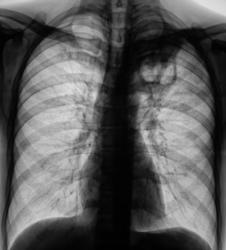

Пациент в 2007, 2008 гг. проходил профилактическую флюорографию - иллюстрации ниже. При прохождении флюорографиив 2009 г. "картинка" резко отличается от предыдущих.

1.Флюорограммы за 2007, 2008 гг. представлены, оценены, как норма.

2. Мужчина, 48 лет.

3. Жалобы на общую слабость. Больше жалоб никаких. В последнее время - кашель, мокрота беловатого цвета, имеются прожилки крови. Внешне - пациент недостаточного питания, анемичен, живет в семье.

По поводу личного мнения - больше склоняюсь, пока, в сторону абсцесса, однако сомнения терзают и весьма.

А разве не похоже на каверну с толстыми стенками?

Очень похоже,но при микроскопии "палки" не выявлены. Фтизиатр занимается пациентом вплотную. Уже рентгенологически обследовано "окружение" пациента, договорились с областной туб. больницей по поводу госпитализации. Но, вот полость какая-то не совсем типичная, хотя локализация и общий вид верхушки прямо указывают на "специфику".

Не должно быть туберкулёзом. Полость большая, а отсевов нет.

Как Вам версия распадающегося рака?

А я так хотела Вас возбудить!😊 Жаль-жаль.Туберкулёз тоже вполне подходит под эту картинку. Хронический очистившийся абсцесс тоже в диф.ряд. Могу и обосновать.